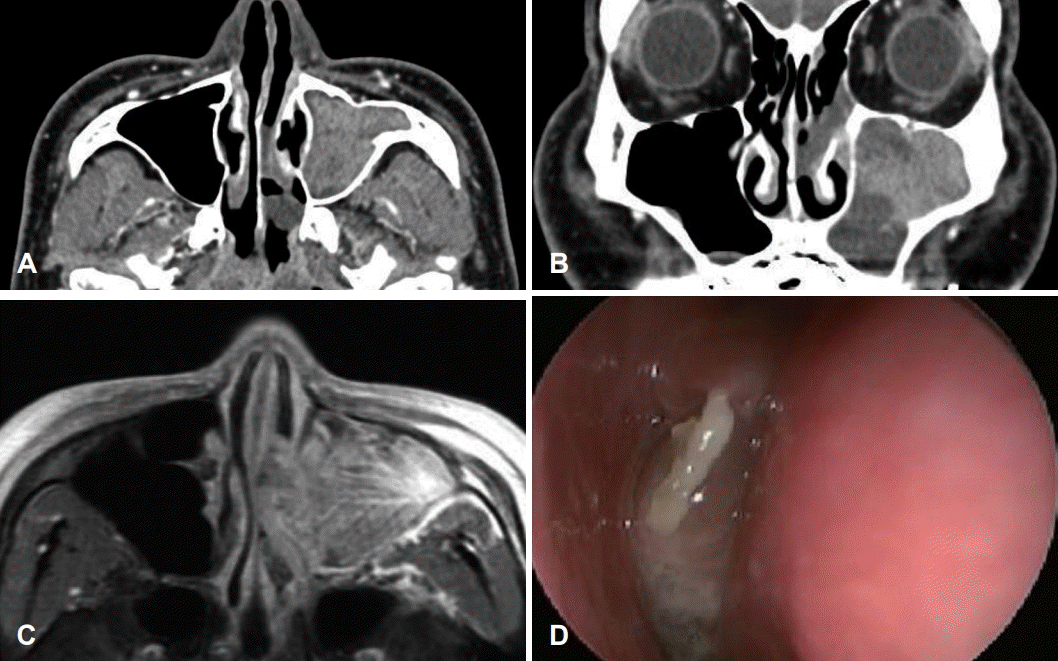

Representative image of a patient who underwent prelacrimal recess approach. Preoperative CT and MRI scans showing a soft tissue density extending from the left maxillary sinus through ostium into the nasal cavity. Axial CT scan shows osteophytic lesion with enhancing soft tissue lesion in the posterolateral aspect of the left maxillary sinus (A). Coronal view image of the same patient (B). Axial view of T1-weighted contrast-enhanced MRI shows heterogenously enhancing soft tissue lesion in left ostiomeatal unit & maxillary sinus (C). Nasal endoscopy showing papillomatous lesion extruding from the middle meatus (D).